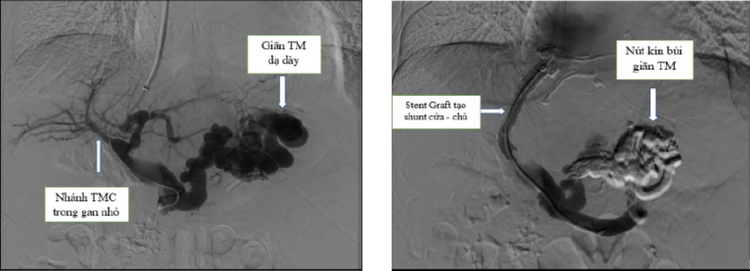

Tại Bệnh viện người bệnh có dấu hiệu sốc mất máu, sau khi được điều trị hồi sức tích cực thoát khỏi tình trạng sốc; người bệnh đã được hội chẩn với chuyên khoa điện quang can thiệp và được thực hiện kỹ thuật TIPS tạo luồng thông cửa chủ kết hợp với nút các búi giãn tĩnh mạch thực quản, cắt nguồn gây chảy máu. Đây là phương pháp điều trị tối ưu đã giúp cho người bệnh thoát khỏi tình trạng chảy máu tái phát.

| Hình ảnh can thiệp TIPS và đặt stent tạo luồng thông cửa chủ thành công - Ảnh BVCC |

Sau can thiệp, người bệnh ổn định, không còn tình trạng chảy máu tiêu hóa, các búi giãn tĩnh mạch thực quản xẹp hoàn toàn.

Người bệnh đã được Ekip Điện quang can thiệp thực hiện kỹ thuật TIPS kết hợp nút tắc hoàn toàn các búi giãn tĩnh mạch gây chảy máu. Sau can thiệp, sức khỏe người bệnh đã ổn định